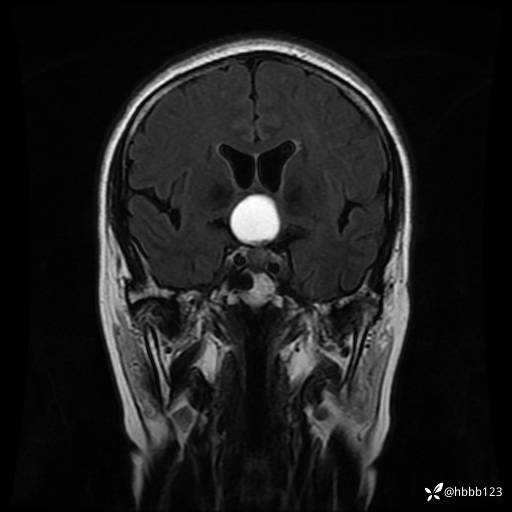

T2 Flair冠状位重建:

T1WI 增强 冠状位重建: